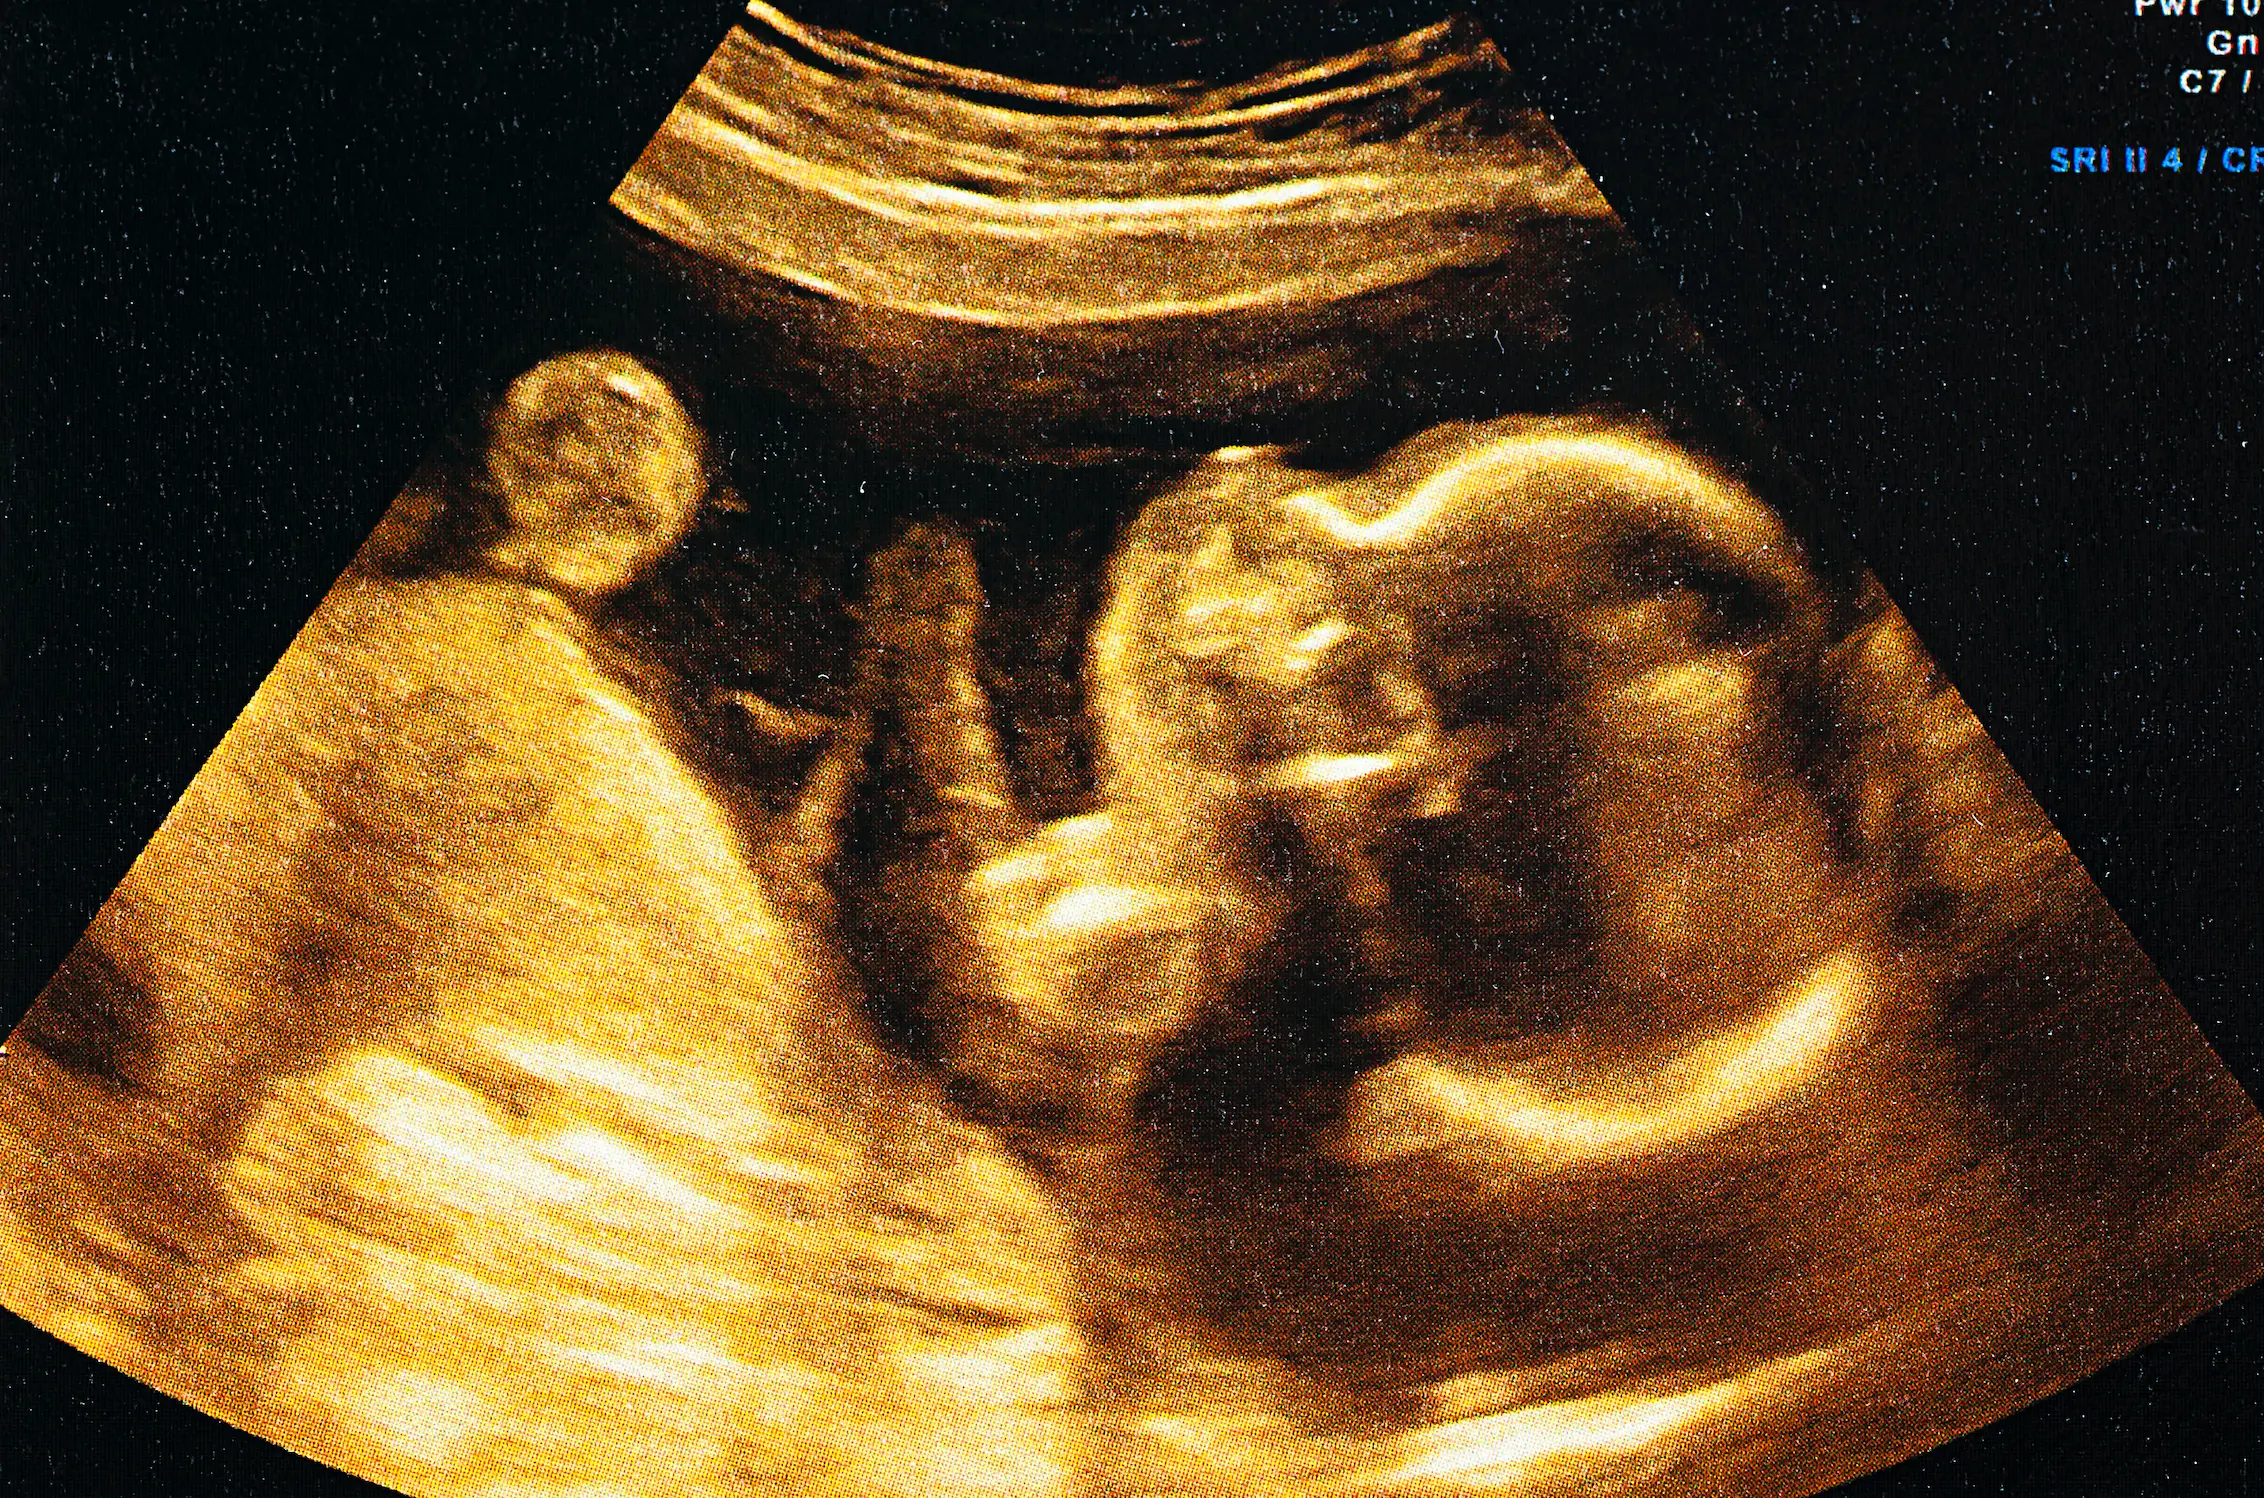

In fact, according to a group of US scientists, heavy drinking during the months prior to impregnation (or conception, whichever your GCSE biology teacher taught you to say...) can affect the development of the child's facial features.

In particular, the growth rate of the babies' eyes, head, mouth and jaw can be damaged as a result of excessive alcohol consumption on the father's part.

This is due to the risk that too much booze can trigger foetal alcohol spectrum disorder (FASD), which affects facial growth in the womb.

It was discovered that the offspring of men that drank were considerably more likely to have smaller eyes, squished faces and smaller mouths.

Their ears were also found further down their heads, compared with babies whose dads did not drink.

And on top of this, these babies were more at risk of developing microcephaly, which sees the underdevelopment of the head and brain.